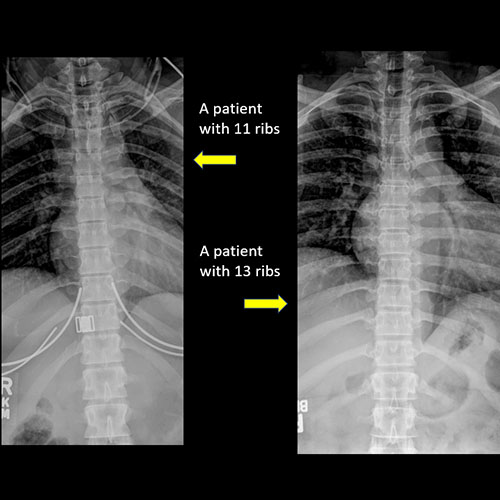

There are more or less than the expected 12 rib-bearing vertebral bodies. [Yes/No]

There are cervical ribs at the cervicothoracic junction, or hypoplastic or rudimentary ribs at the thoracolumbar junction. [Yes/No]